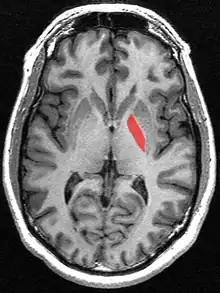

Globus pallidus (in red) shown within the brain

The globus pallidus (GP), also known as paleostriatum or dorsal pallidum,[1] is a subcortical structure of the brain. It consists of two adjacent segments, one external, known in rodents simply as the globus pallidus, and one internal, known in rodents as the entopeduncular nucleus. It is part of the telencephalon, but retains close functional ties with the subthalamus in the diencephalon – both of which are part of the extrapyramidal motor system.[2] The globus pallidus is a major component of the basal ganglia, with principal inputs from the striatum, and principal direct outputs to the thalamus and the substantia nigra. The latter is made up of similar neuronal elements, has similar afferents from the striatum, similar projections to the thalamus, and has a similar synaptology. Neither receives direct cortical afferents, and both receive substantial additional inputs from the intralaminar thalamus.